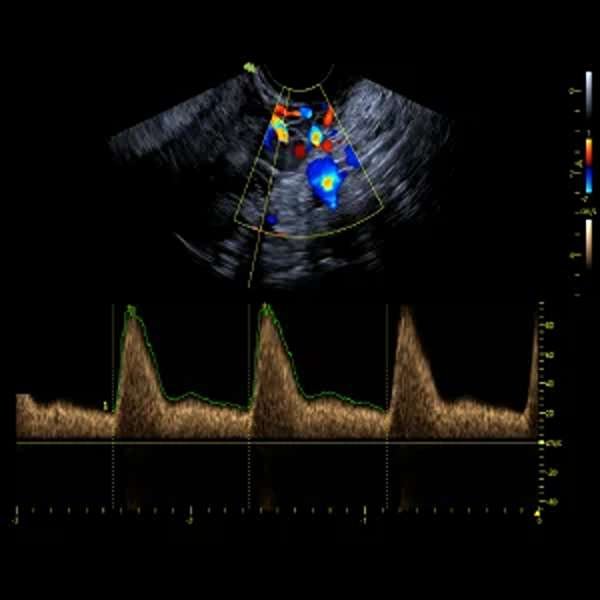

Ecografía Transvaginal Doppler

La ecografía transvaginal Doppler es un estudio avanzado que, además de proporcionar imágenes detalladas del útero, los ovarios y el endometrio, evalúa el flujo sanguíneo en la zona pélvica. Es clave para detectar alteraciones vasculares, como tumores, quistes o problemas en la circulación que puedan afectar la fertilidad o el embarazo. Este procedimiento es seguro, indoloro y de gran precisión, permitiendo un diagnóstico más completo en casos de endometriosis, síndrome de ovario poliquístico o control de embarazos de alto riesgo.